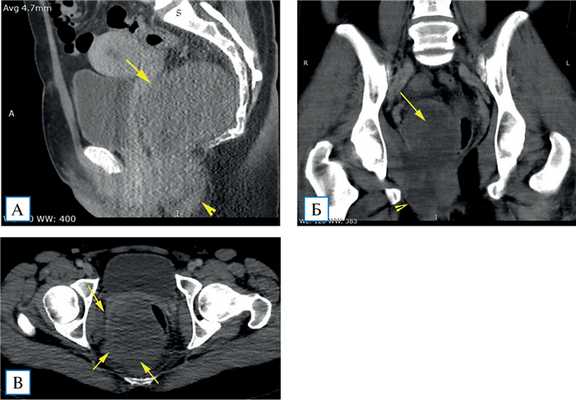

Для определения характера выявленного образования назначены мультисрезовая компьютерная томография (МСКТ) и МР-исследование. На 2-й день госпитализации выполнена МСКТ с болюсным контрастированием: в пресакральном пространстве, больше справа, оттесняя шейку матки кпереди и прямую кишку влево, определяется объемное образование размерами 65×70×135 мм, пролабирующее нижним краем в седалищно-анальную ямку. Контуры опухолевидного образования четкие, ровные. Плотность его близка к жидкостной (до +28 HU), структура неоднородная, складывается впечатление о наличии слоистости либо внутренних септ. Выраженного накопления контрастного вещества опухолью достоверно установить не удалось. Отмечены артефакты от костей таза, затрудняющие анализ изображений. Жидкости в малом тазу не выявлено (рис. 1).

Рис. 1. Компьютерные томограммы малого таза в венозную фазу контрастирования: мультипланарные реконструкции в сагиттальной (А), фронтальной (Б) и аксиальной (В) плоскостях

Примечание. Определяется объемное образование, слабо накапливающее контрастный препарат, имеющее связь с диафрагмой таза (А, Б, наконечник стрелки). Оценить инвазию образования в прямую кишку и латеральную стенку таза не представляется возможным (А, Б, В, стрелки).